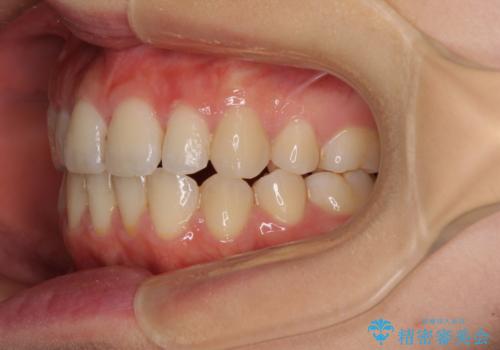

前歯2本が欠損 抜歯矯正でデコボコを治す

抜歯矯正を行ったことで、デコボコが改善されただけでなく、口元も下がったことで口が閉じやすくなりました。